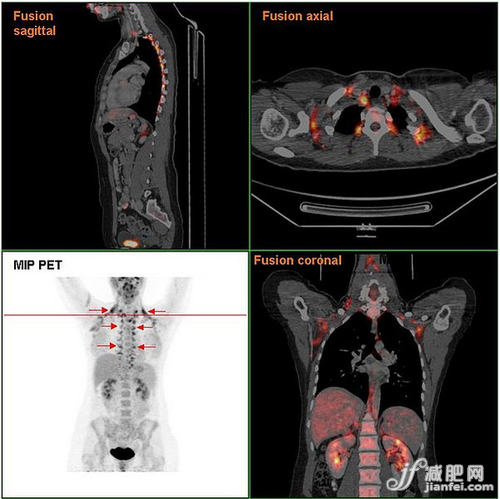

女性棕色脂防組織分布的PET/CT 掃描結(jié)果圖。